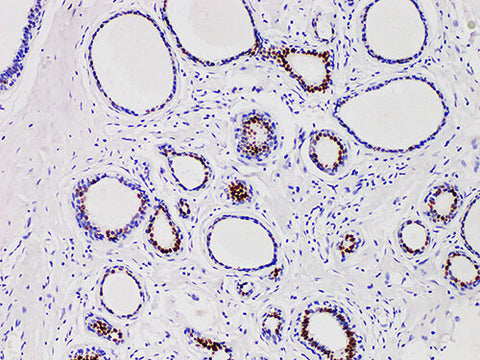

Applications IHC-P

Tissue Specificity Breast cancer

Progesterone receptor (PR) has two isomers, pra (94kda) and pRb (114kda), whose function is that transcription factors exist in normal endometrial and mammary epithelial cells after ligand activation. Recently, a large number of studies on breast cancer have shown that most of the ER and PR positive data are effective in endocrine therapy, with high remission rate, low recurrence rate and good prognosis. Even if there is only one positive patient in ER or PR, its prognosis is better than the two all negative patients, so PR has become one of the routine examination items for breast cancer patients.